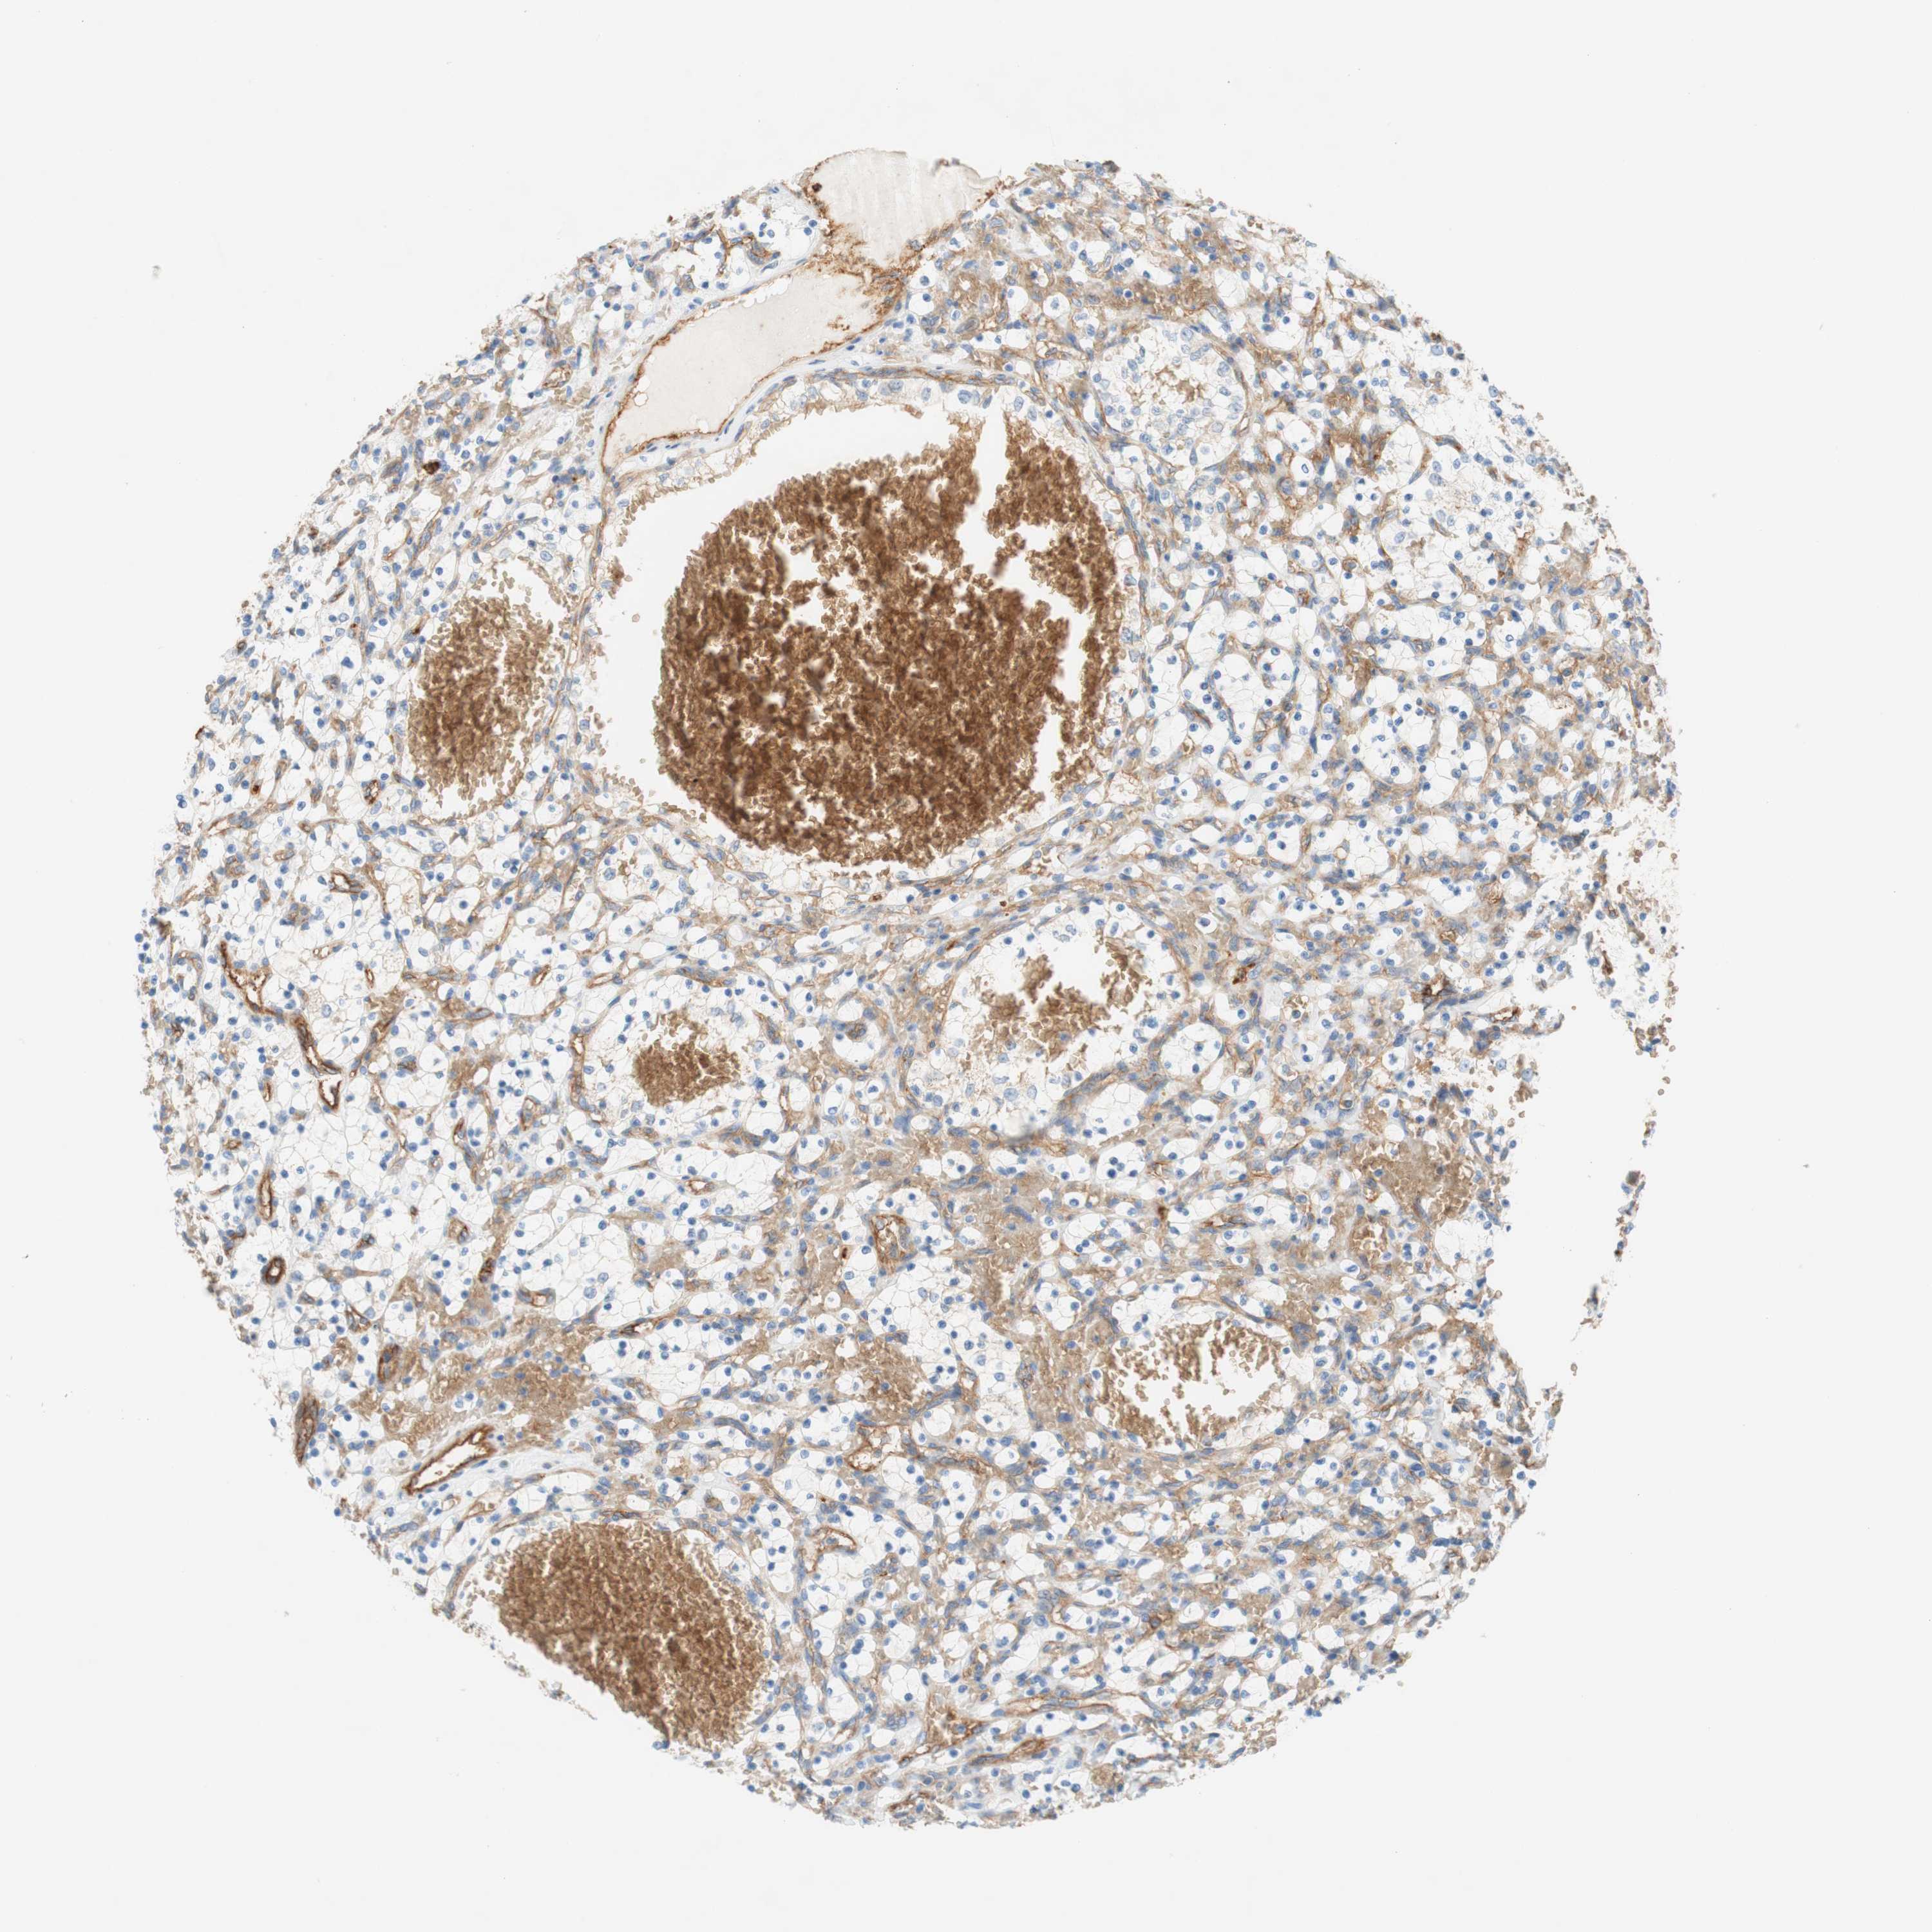

CANCER RENAL CANCER Show tissue menu

KICH TCGA KIRC TCGA KIRC VALIDATION KIRP TCGA PROTEIN RCC CPTAC PROTEIN EXPRESSION